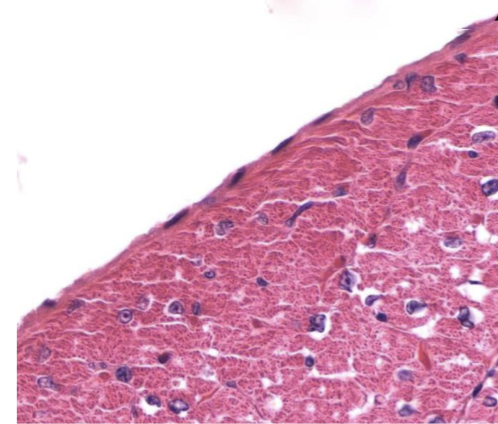

Identifique tipo de tejido conectivo

reticular

Indique sitio anatómico dónde se encuentra

higado